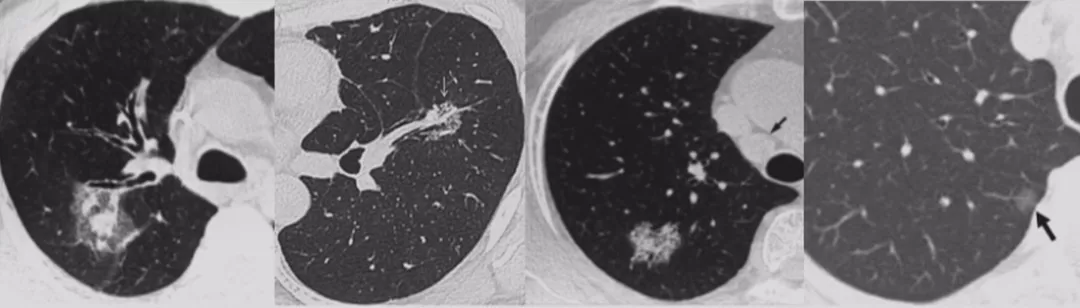

按照肺结节的密度,可分为实性结节、部分实性结节、亚实性或混合性结节、无实性或磨玻璃结节;根据肺结节的数目,可以分为孤立性肺结节(SPN)和多发性肺结节(MPN)。最近多发性肺结节的病人有所增加,临床上针对这类患者的诊断和处理方面还存在许多困难。

如上图所示,一般来说这么小的病灶我们可能忽略,但这个病人做了手术,不仅是恶性肿瘤,而且是微浸润腺癌。实际上我们在临床上要把这么多结节甄别出来,是十分具有挑战性的。病人一旦患有肺结节,也面临着很多问题,比如焦虑、心理压力等。所以我们既不能过度诊断,但也不能延误诊断。

在临床上经常手术切除后发现是AAH,关于AAH的病人是否需要手术还存在很大的争议,有的认为不需要手术,观察就可以。那么我们在术前怎么评判是否为AAH?其实具有一定特征。一般来说,多位于肺外周,多<5mm,圆形或类圆形,边界清楚,多发更常见,绝大部分是均匀的纯磨玻璃影,里边没有实性成分。组织学检查AAH呈轻度到中度非典型立方柱状上皮细胞沿肺泡和呼吸性细支气管上皮增殖,无浸润,这样在临床上诊断AAH应该没有问题。但是,如下图所示,这个病人是多灶性病变,现在多灶性结节有所增多,会给临床的处理上带来一定压力。

小细胞肺癌以中央型多见,但是也有少数为周围型病灶。多为单个实性结节或肿块,可见分叶、毛刺、血管集束征、胸膜牵拉征。实际上我们很难从影像学上判断出小细胞肺癌的病理类型,往往是活检或者手术以后才能证实。如下图示,这属于I期的小细胞肺癌,进行手术的效果非常好。所以对于周围型小细胞肺癌,如果在结节很小的时候判断出来就做了手术,疗效非常好。我们知道小细胞肺癌是肺癌中治疗效果最差的,恶性程度是最高的。如果早期手术,仍然能够起到很好的效果。

肺部转移性恶性结节常为多发,但也可见到单个转移性实性结节病灶,要注意这一点。